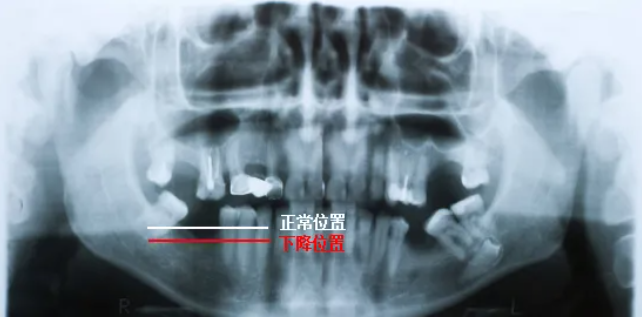

🔎牙周情况

△正常情况下,牙槽骨高度位于牙根与牙冠的交界处下方一点(白色线标注位置)。